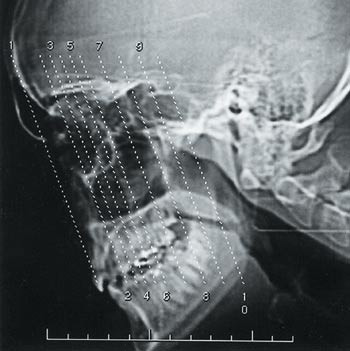

CT-undersøkelsene ble utført med en HiSpeed CT/i-maskin (GE Medical Systems, Milwaukee, WI, USA) med koronal snittføring og hyperekstendert nakke. Standarddose-CT ble utført med ca. 23 snitt med snittykkelse 3 mm. Snittintervallet var 3 mm gjennom det ostiomeatale kompleks og 5 mm gjennom resterende bihuler. Eksponeringen ble foretatt med strømstyrke 200 – 240 mA og rørspenning 120 kilovolt (kV) i ett sekund. Ved lavdose-CT ble det tatt ti koronale snitt med snittykkelse 1 mm, kV 120, mA 40 og eksponeringstid ett sekund. Det første snittet ble lagt gjennom midtre del av frontalsinus foran øyets linse. Snitt nummer to ble lagt 15 mm bak første snitt og bak øyets linse for å unngå direkte bestråling. Snittene 3 – 7 ble lagt gjennom det ostiomeatale kompleks med snittavstand 5 mm. De tre siste snittene ble lagt gjennom bakre etmoidalceller og sphenoidalsinus med en snittavstand på 10 mm (fig 1). Bildene ble rekonstruert med kantforsterkningsalgoritme og avbildet med bildevinduet (Window Width) 2000 Hounsfield-enheter (HU) og bildesenter (Window Level) 250 HU. Stråledosene ble for CT-undersøkelsene utregnet med dataprogrammet CTDOSE og for røntgenundersøkelsen med programmet XDOSE (National Radiation Laboratory, Christchurch, New Zealand).

Sensitivitet og spesifisitet for røntgen bihuler og lavdose-CT fremgår av tabell 1. Ved røntgen bihuler var spesifisiteten høy, men sensitiviteten lav (< 50 %) for alle sinusgrupper bortsett fra kjevehulene, hvor sensitiviteten var 80 %. For lavdose-CT var den samlede sensitivitet og spesifisitet for tilstedeværelse eller fravær av sinusitt henholdsvis 95 % og 97 %. Lavdose-CT var ved denne problemstillingen tilnærmet like nøyaktig som standarddose-CT. Den lave mA-verdien med økte artefakter gav få tolkingsproblemer (fig 2).